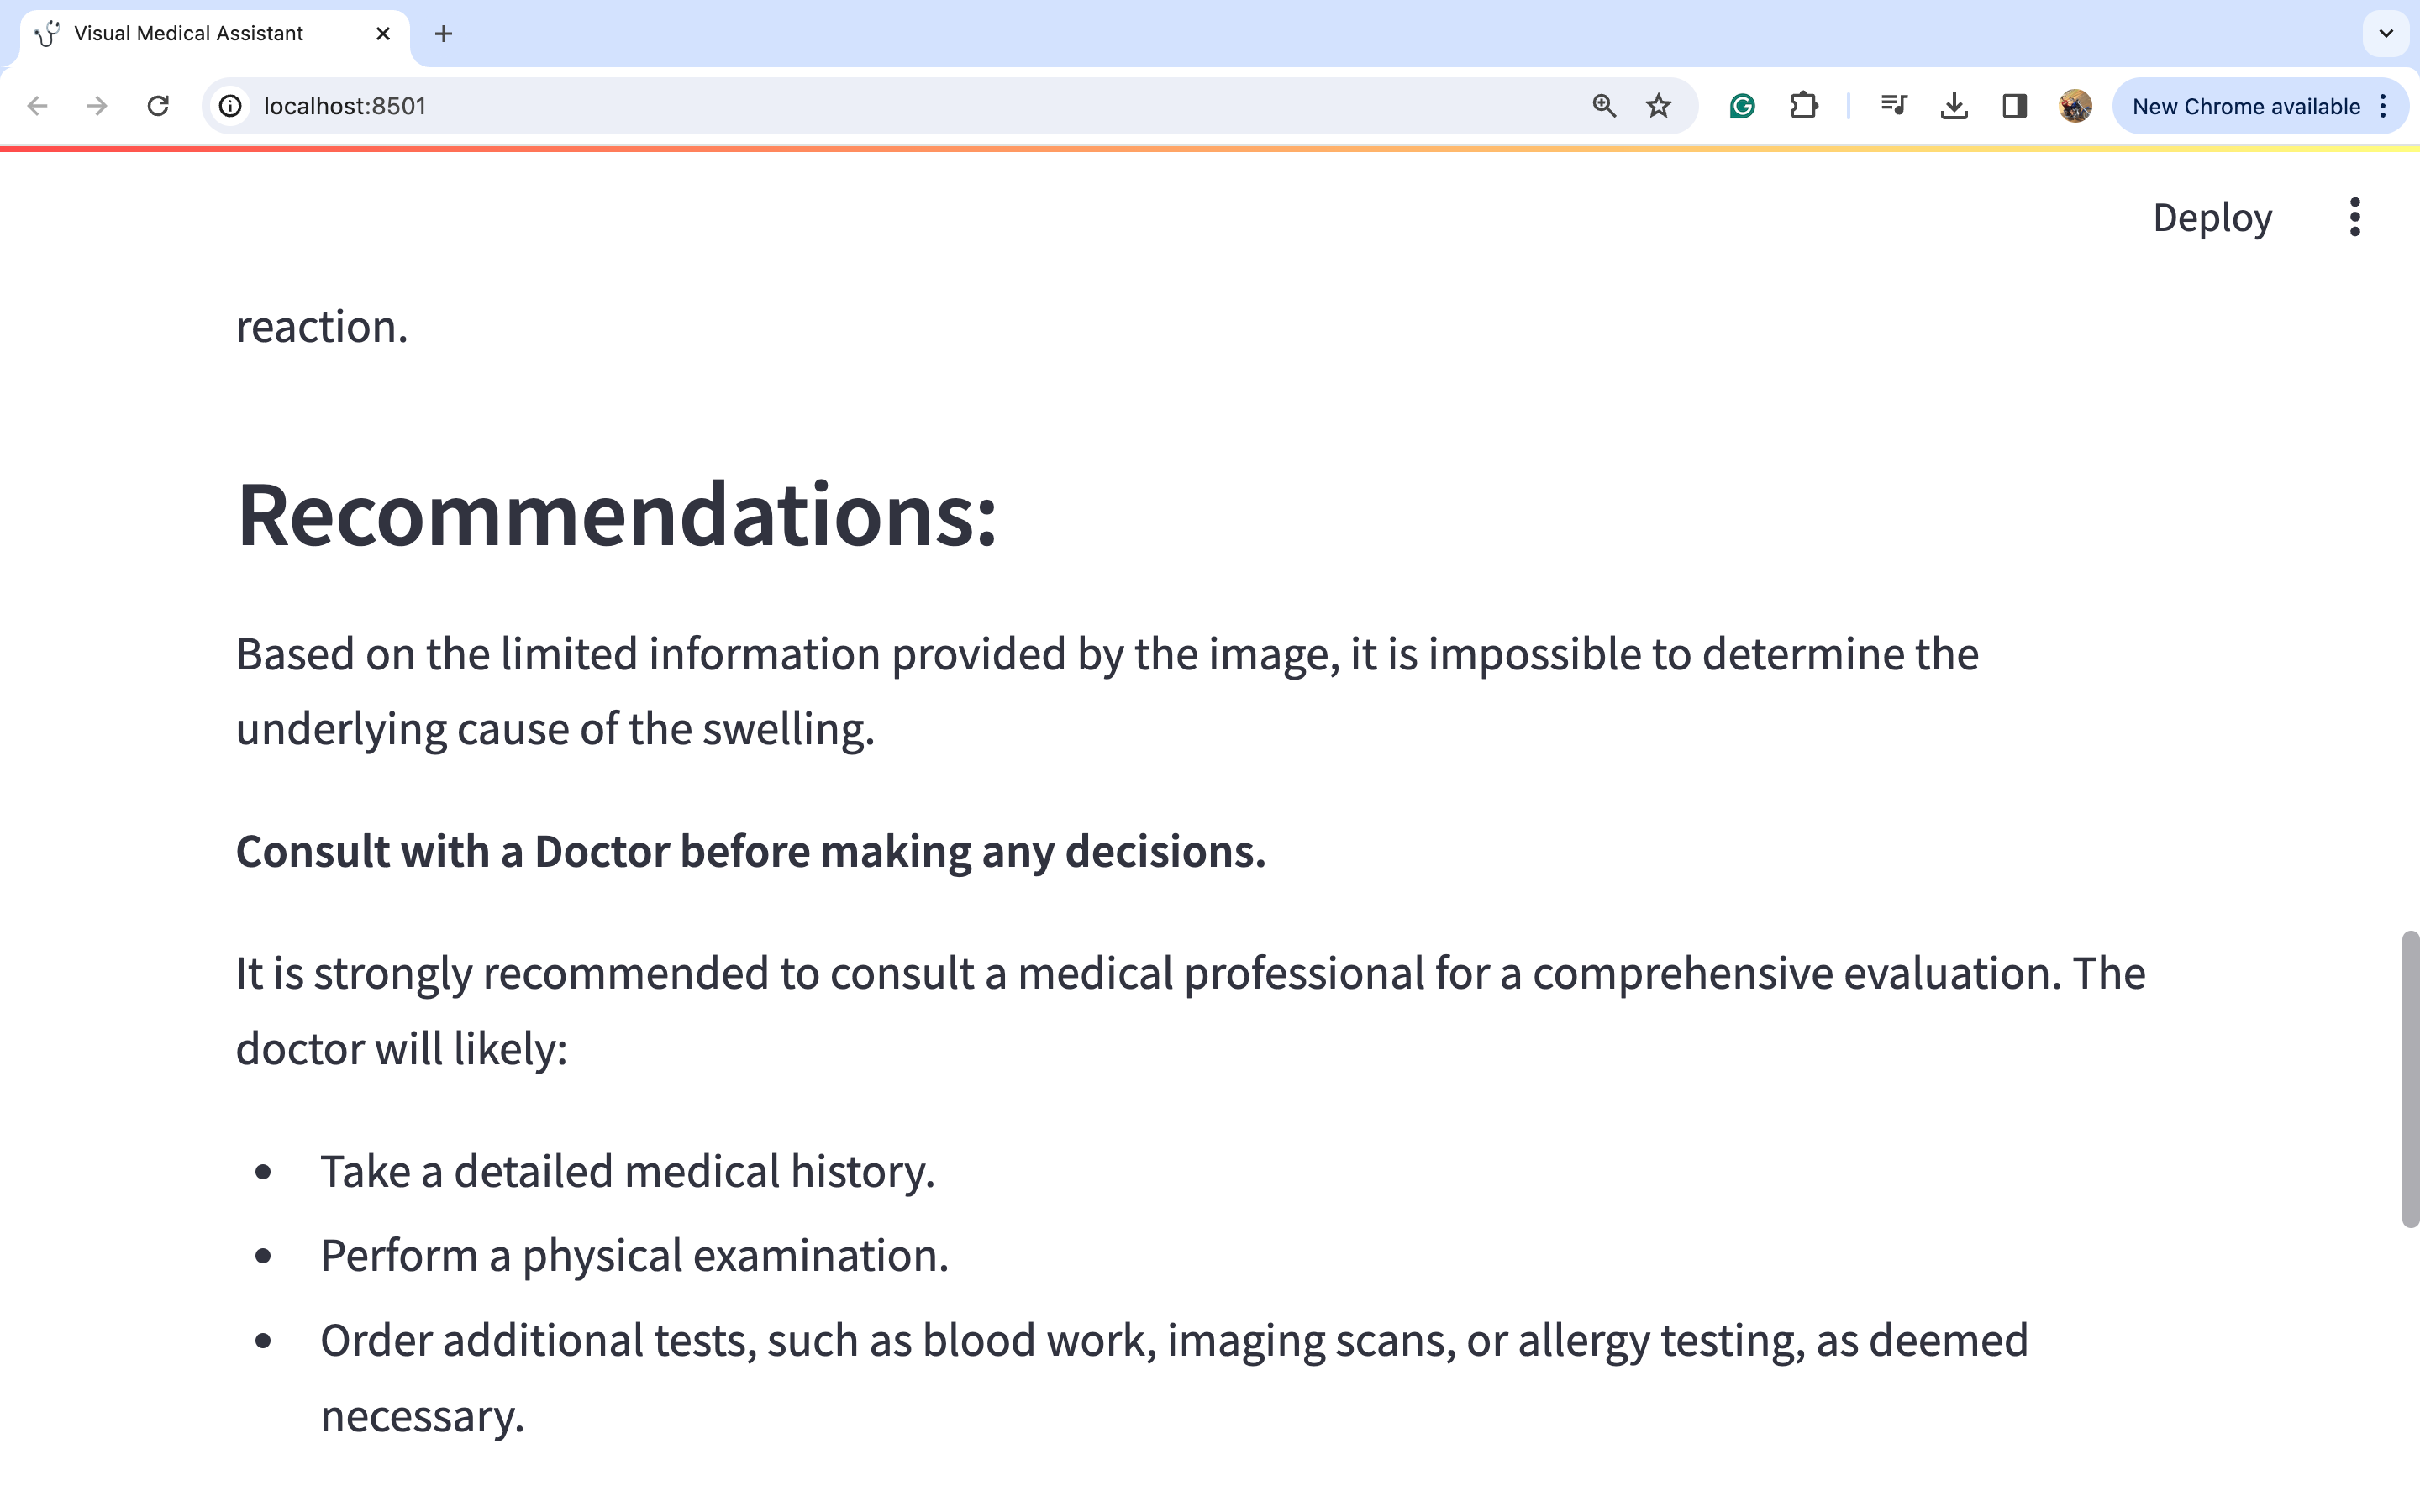

图片2:

因此,我们可以通过观察图片来进行深入的详细分析,从而得出可能的医疗诊断。我们可以看到模型如何捕捉到左脚肿胀的问题。模型建议咨询医生,因为仅仅通过观察这种肿胀很难得出很多结论。然而,我们可以看到一些治疗选择,如使用压缩包和抬高左脚以减轻肿胀,在这种情况下似乎是合理的选择。